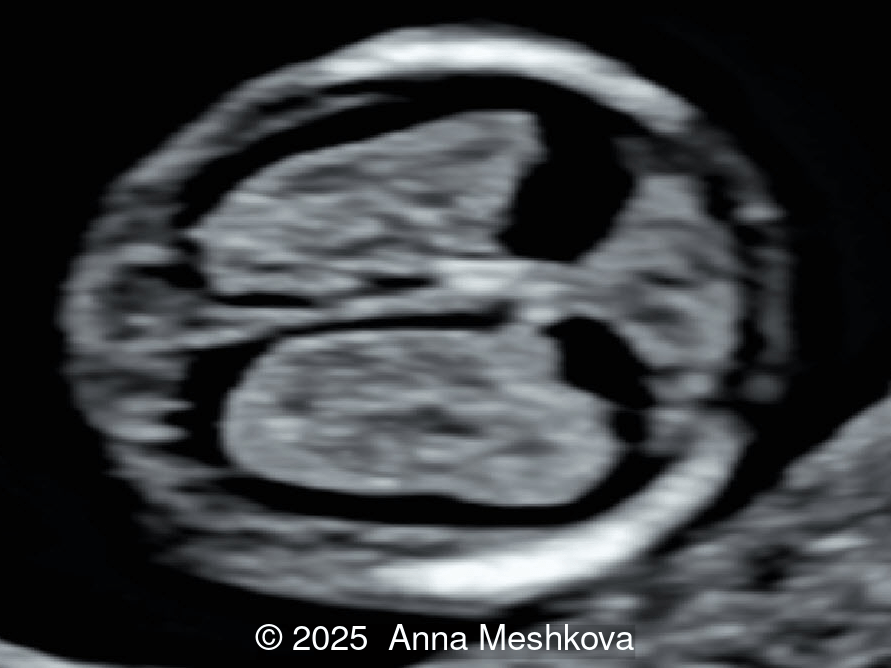

Image 3

• Image 3, Video 1: Mid-sagittal image demonstrating the mid brain and brain stem displaced posteriorly, known as the "crash" sign. Intracranial translucency is difficult to visualize.

5.  The Crash Sign describes the posterior displacement and deformation of the mesencephalon against the occipital bone due to reduced intracranial pressure caused by cerebrospinal fluid leakage. This is a promising early marker seen in a majority of first-trimester open spina bifida cases.  During this posterior displacement, the mesencephalon meets the only firm cranial structure on its way, the occipital bone, and is compressed against it.  On mid-sagittal view the brainstem is thickened and shifted posteriorly [6].